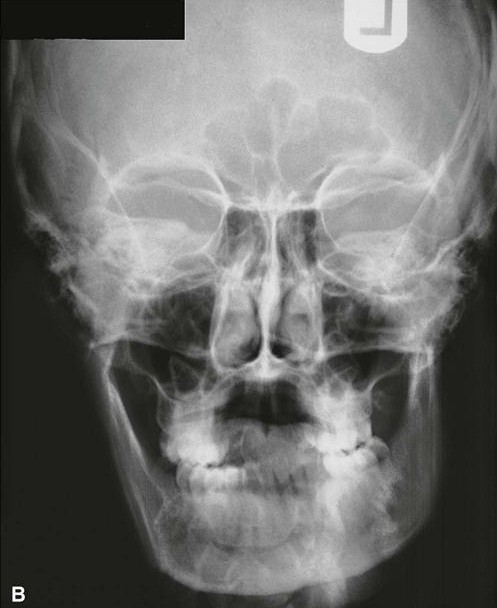

1. Radiographs:

-PA VIEW:

PA View:Medio-lateral extent of bony growth can be seen on this radiograph.